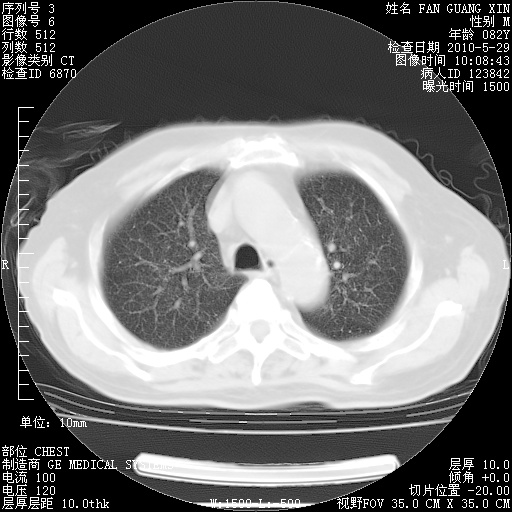

再治疗10天后的肺部CT

从白细胞总数和中性比例看好像合并感染。肺部纹理好像比上次多,支气管炎?其他感染?

阅读此次胸部CT,肺间质渗出性改变较入院时有吸收。目前从体温、白细胞、中性分叶明显增高,肯定存在细菌感染(发生医院感染哦,若无消化道及泌尿系统等感染的依据,肺部感染可能大)。若你院头孢哌酮舒巴坦钠耐药率较高,同意你的方案,若48小时体温仍高,可考虑使用碳青霉稀类抗菌药物,同时可予超声雾化、注意滴数时加大液体量。白蛋白33.30g/L较低哦,需加强营养等支持治疗。